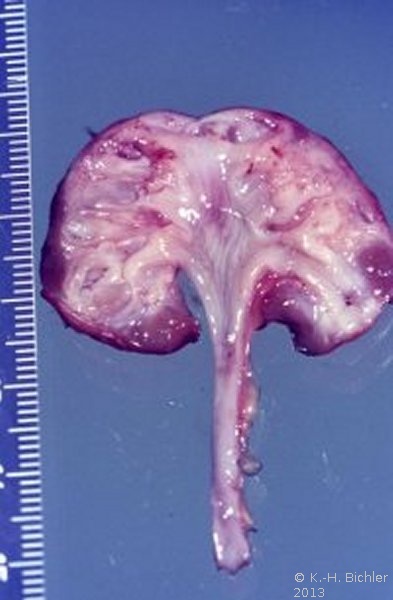

Es handelt sich pathologisch-anatomisch um eine kleine Niere mit einem Gewicht um 30g. Dabei sind die funktionellen Elemente (Renculi) numerisch reduziert auf 3 bis 5, normal 12 bis 14. Die Organanteile sind aber normal entwickelt (

Im Gegensatz zum in der Abbildung beschriebenen Beispiel besteht bei der Aplasie oder Dysplasie ein unvollständiges Gewebe mit erhaltenem fetalen Anteil (Abbildung 21).

Die echte Hypoplasie hat keine Komplikationen wie Hypertonie. Sie wird in der Regel zufällig entdeckt, im Gegensatz zur einseitigen pyelonephritischen Zwergniere mit Hypertonie. Die echte hypoplastische Niere ist selten. Zollinger fand unter 10.000 Obduktionen eine hypoplastische Niere. Die erworbenen Zwergnieren infolge entzündlicher oder vaskulärer Ursachen sind dagegen häufiger.